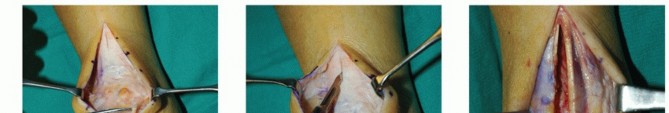

DEFINITION Subluxation or dislocation of the peroneal tendon is a relatively uncommon injury, with the majori…